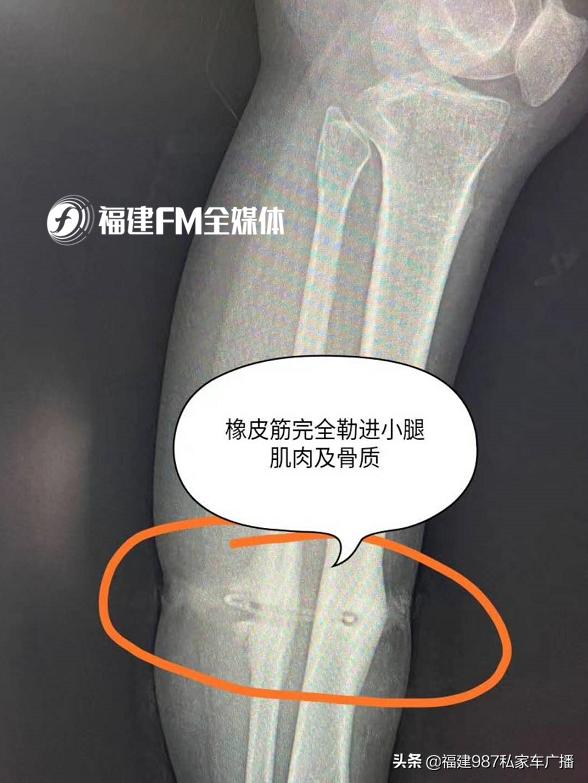

许医生根据患者情况和家属的描述决定对她进行CT核磁共振,一查才发现导致患者伤口不断流脓的“元凶”竟是一段打了结的橡皮筋,而此时这条橡皮筋已经有部分和骨头“紧密相连”。

“我们腿上布有血管,这橡皮筋是深深地勒进去的,我就怕血管被勒了,一旦橡皮筋被拔出,血管就炸了。还有一旦血管勒断了,导致组织坏死,结果只能截肢。万幸的是橡皮筋只勒到骨头,血管躲在两个骨头之间逃过一劫。”

许医生表示,这名患者的情况十分罕见,因为橡皮筋需要日积月累才能“切开”皮肤,“切”过肌肉,最终嵌进骨头。

虽然,症结已经找到,但是考虑到橡皮筋有部分与骨头相连,手术难度并不低。好在许医生在术前做好充足的检查和准备,并在麻醉科医生的协助下才将异物顺利取出,避免了橡皮筋引起的“进一步破坏”,保住了患者这条腿。